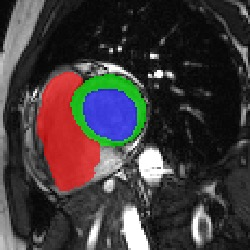

Transformers, the default model of choices in natural language processing, have drawn scant attention from the medical imaging community. Given the ability to exploit long-term dependencies, transformers are promising to help atypical convolutional neural networks (convnets) to overcome its inherent shortcomings of spatial inductive bias. However, most of recently proposed transformer-based segmentation approaches simply treated transformers as assisted modules to help encode global context into convolutional representations without investigating how to optimally combine self-attention (i.e., the core of transformers) with convolution. To address this issue, in this paper, we introduce nnFormer (i.e., Not-aNother transFormer), a powerful segmentation model with an interleaved architecture based on empirical combination of self-attention and convolution. In practice, nnFormer learns volumetric representations from 3D local volumes. Compared to the naive voxel-level self-attention implementation, such volume-based operations help to reduce the computational complexity by approximate 98% and 99.5% on Synapse and ACDC datasets, respectively. In comparison to prior-art network configurations, nnFormer achieves tremendous improvements over previous transformer-based methods on two commonly used datasets Synapse and ACDC. For instance, nnFormer outperforms Swin-UNet by over 7 percents on Synapse. Even when compared to nnUNet, currently the best performing fully-convolutional medical segmentation network, nnFormer still provides slightly better performance on Synapse and ACDC.